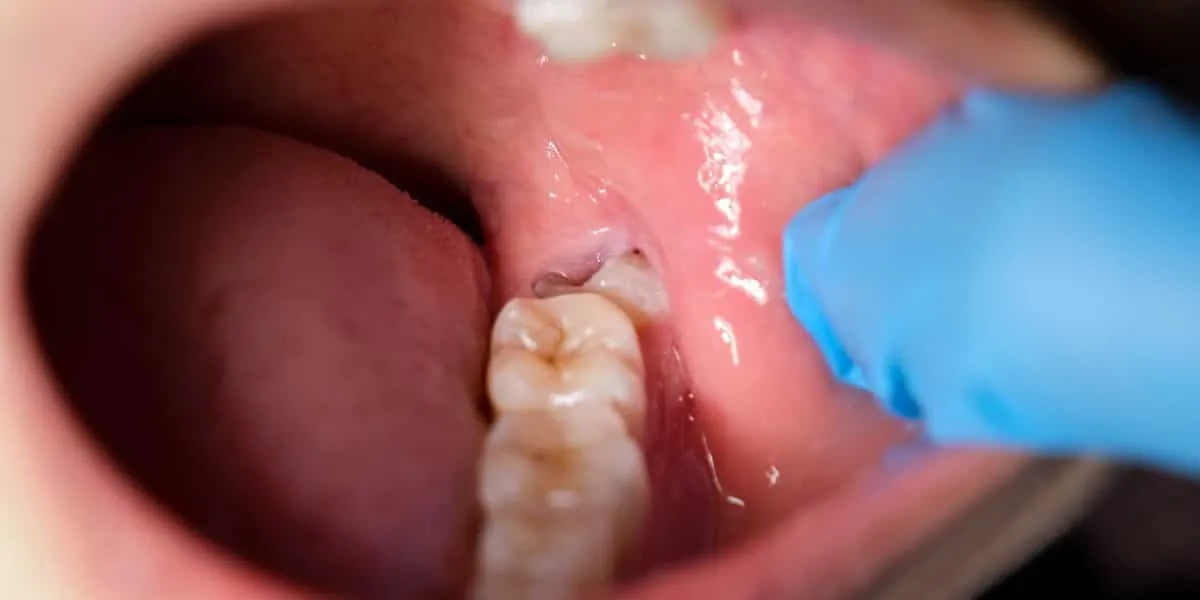

- نهفتگی دندان عقل: گاهی اوقات، دندان عقل به طور کامل رشد نمیکند و زیر لثه گیر میکند. این وضعیت میتواند باعث درد، عفونت و حتی آسیب به دندانهای کناری شود.

- ایجاد عفونت و التهاب لثه: رشد ناقص دندان عقل، محل مناسبی برای تجمع باکتریها و ایجاد عفونت لثه فراهم میکند که با علائمی مانند درد، تورم، بوی بد دهان و خونریزی لثه همراه است.

- عفونت یا ترشح چرک از لثه